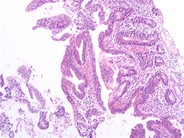

EATL Type I